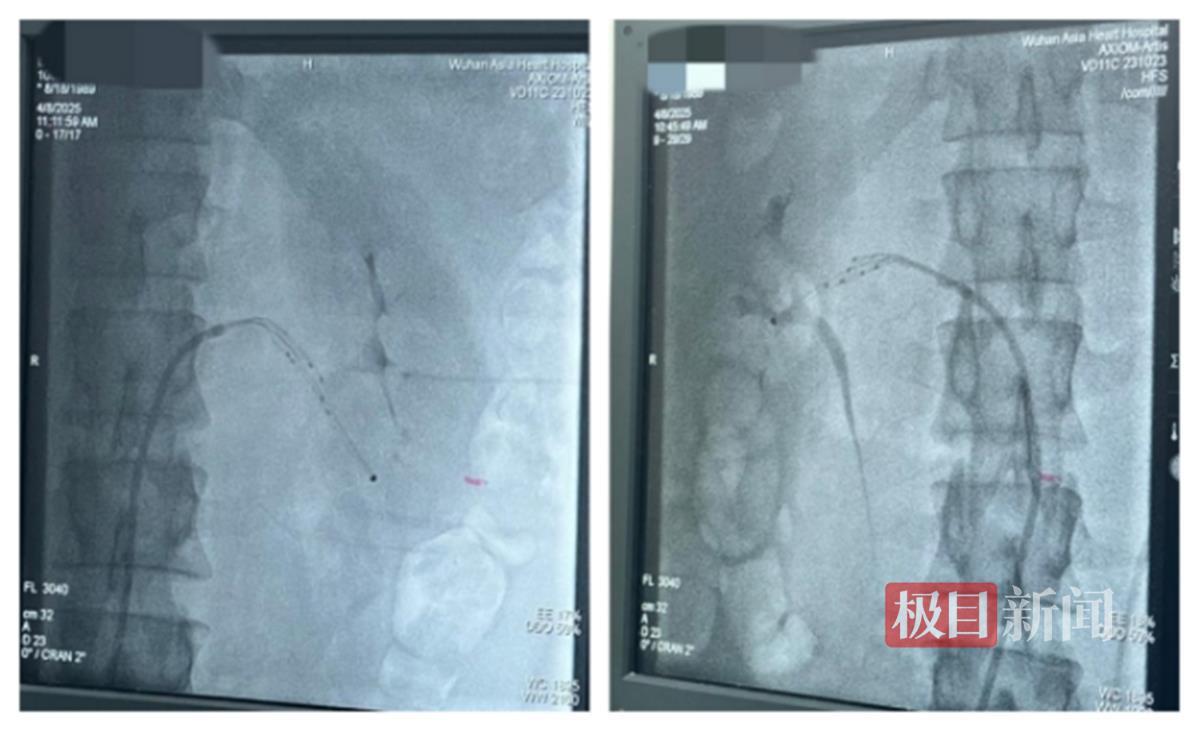

综合评估后,团队决定采用经皮肾动脉交感神经射频消融术,给苏先生“降血压”。近日,该院心内科宋丹主任、熊岗主任联手手术,通过股动脉穿刺,将导管送达肾动脉,共消融37个靶点,抑制过度兴奋的交感神经,让血压逐渐降下来。

术中影像